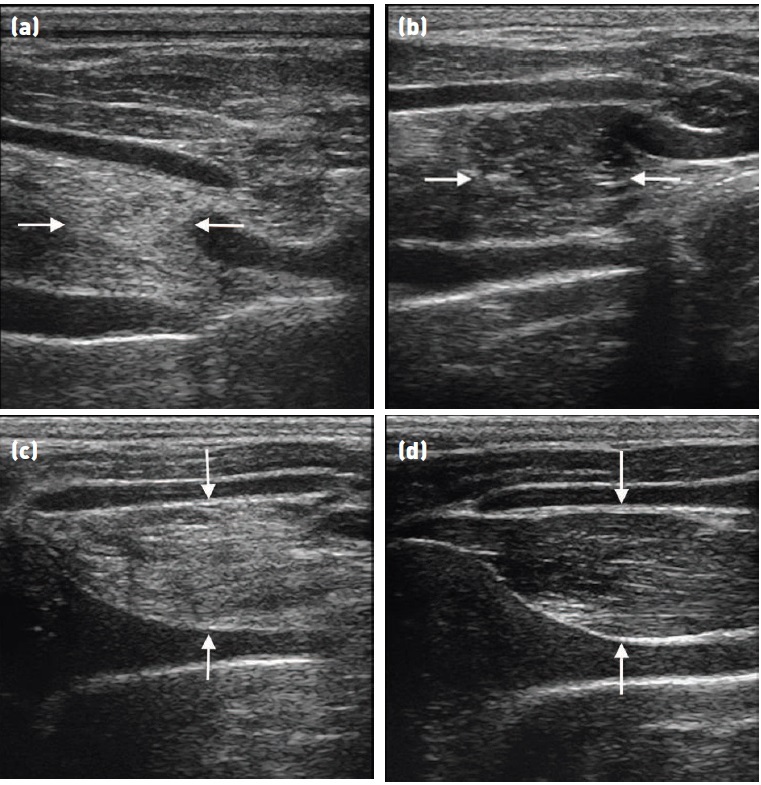

Fig 8: Comparison of echogenicity of the cricoarytenoideus lateralis and vocalis (arrows)

and cricoarytenoideus dorsalis (arrowheads) musculature. Horses with recurrent

laryngeal neuropathy have increased echogenicity and more homogeneous echogenicity

of the cricoarytenoideus lateralis and cricoarytenoideus dorsalis muscles. Dorsal plane

ultrasound images of the cricoarytenoideus lateralis muscle of (a) a horse with recurrent

laryngeal neuropathy and (b) a normal horse. Transverse plane ultrasound images of the

cricoarytenoideus lateralis and vocalis muscles of (c) a horse with recurrent laryngeal

neuropathy and (d) a normal horse. Dorsal plane ultrasound images of the cricoarytenoideus

dorsalis muscle of (e) a horse with recurrent laryngeal neuropathy and (f) a normal horse. In

the dorsal plane images, rostral is to the left and caudal is to the right and in the transverse

plane images, dorsal is to the left of the image and ventral is to the right